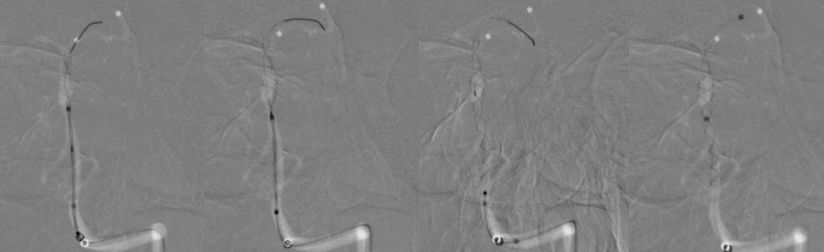

1、患者全身麻醉,右侧股动脉穿刺置入8F动脉鞘,5F中间导管携带6F长鞘超选入左侧椎动脉,行造影及三维旋转寻找最佳工作角度(图8)。

图8

2、调整至合适的工作角度后,撤出5F中间导管,将5F Navien 通过6F长鞘置入左侧V3段。路图引导下由2 m Synchro-14微导丝将T-track支架微导管超选进左侧大脑后动脉P2段(图9)。

图9

3、多个投射角度辅助下,将一枚3x35 mm的Tubridge支架经T-track支架微导管缓慢释放(图10)。

图10